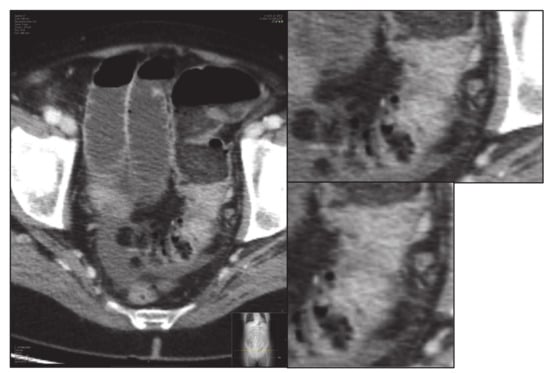

- Third, the screen zoom is adjusted by enlarging the image and an image of the segmented and enlarged tumour is saved: “small-delimited.tiff” (i.e., Figure 3).